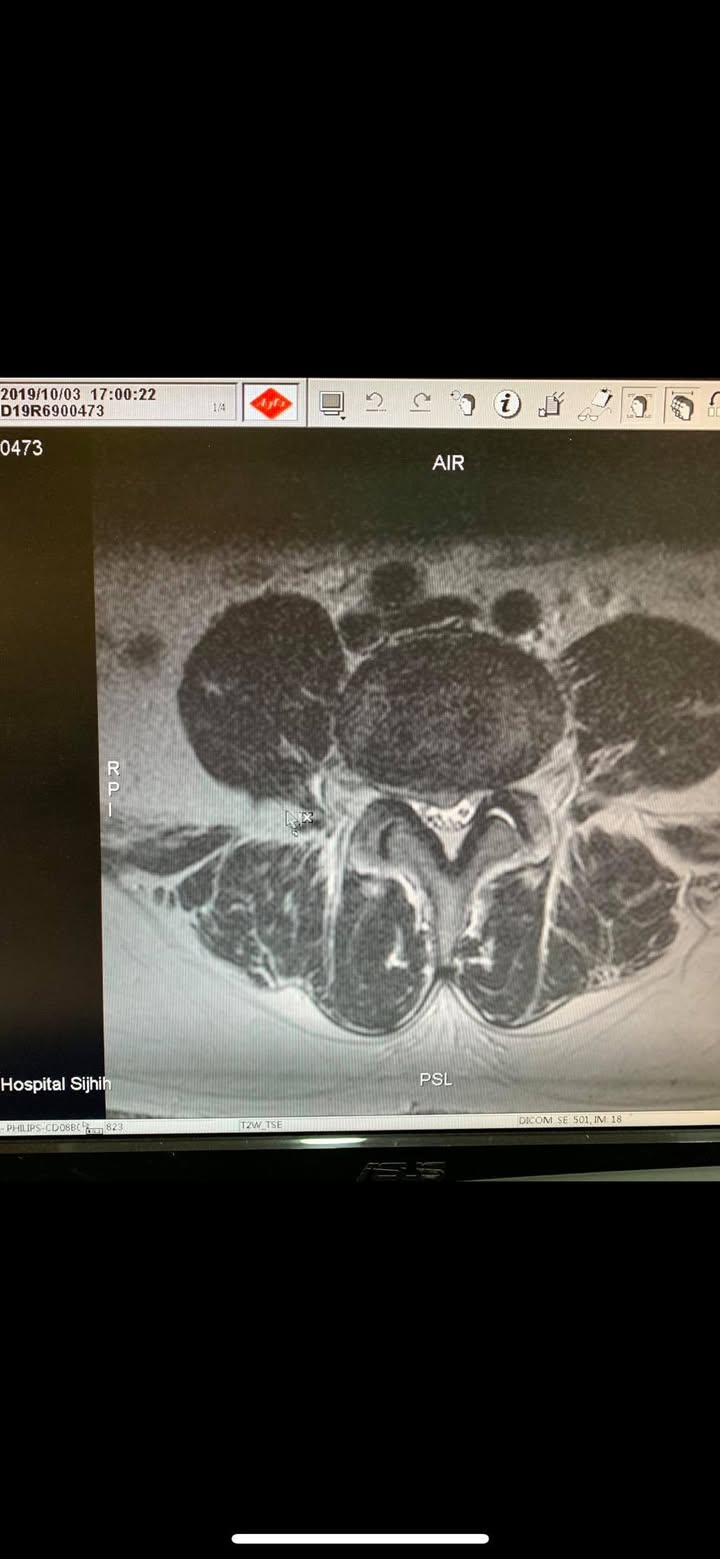

再度逆轉勝!腰椎治療醫案

原本痛到懷疑人生都想去手術了

八週治療後生路活虎!還可以腳踏車去海

邊逛逛,唐先生的苦與樂,只有當事人可

以瞭解啊!!

🆘 什麼情況下需要開刀?

長期保守治療無效者,且經 CT 或MRI檢查明確診斷,或出現大小便失禁,跟肌肉萎縮患者應接受手術治療。